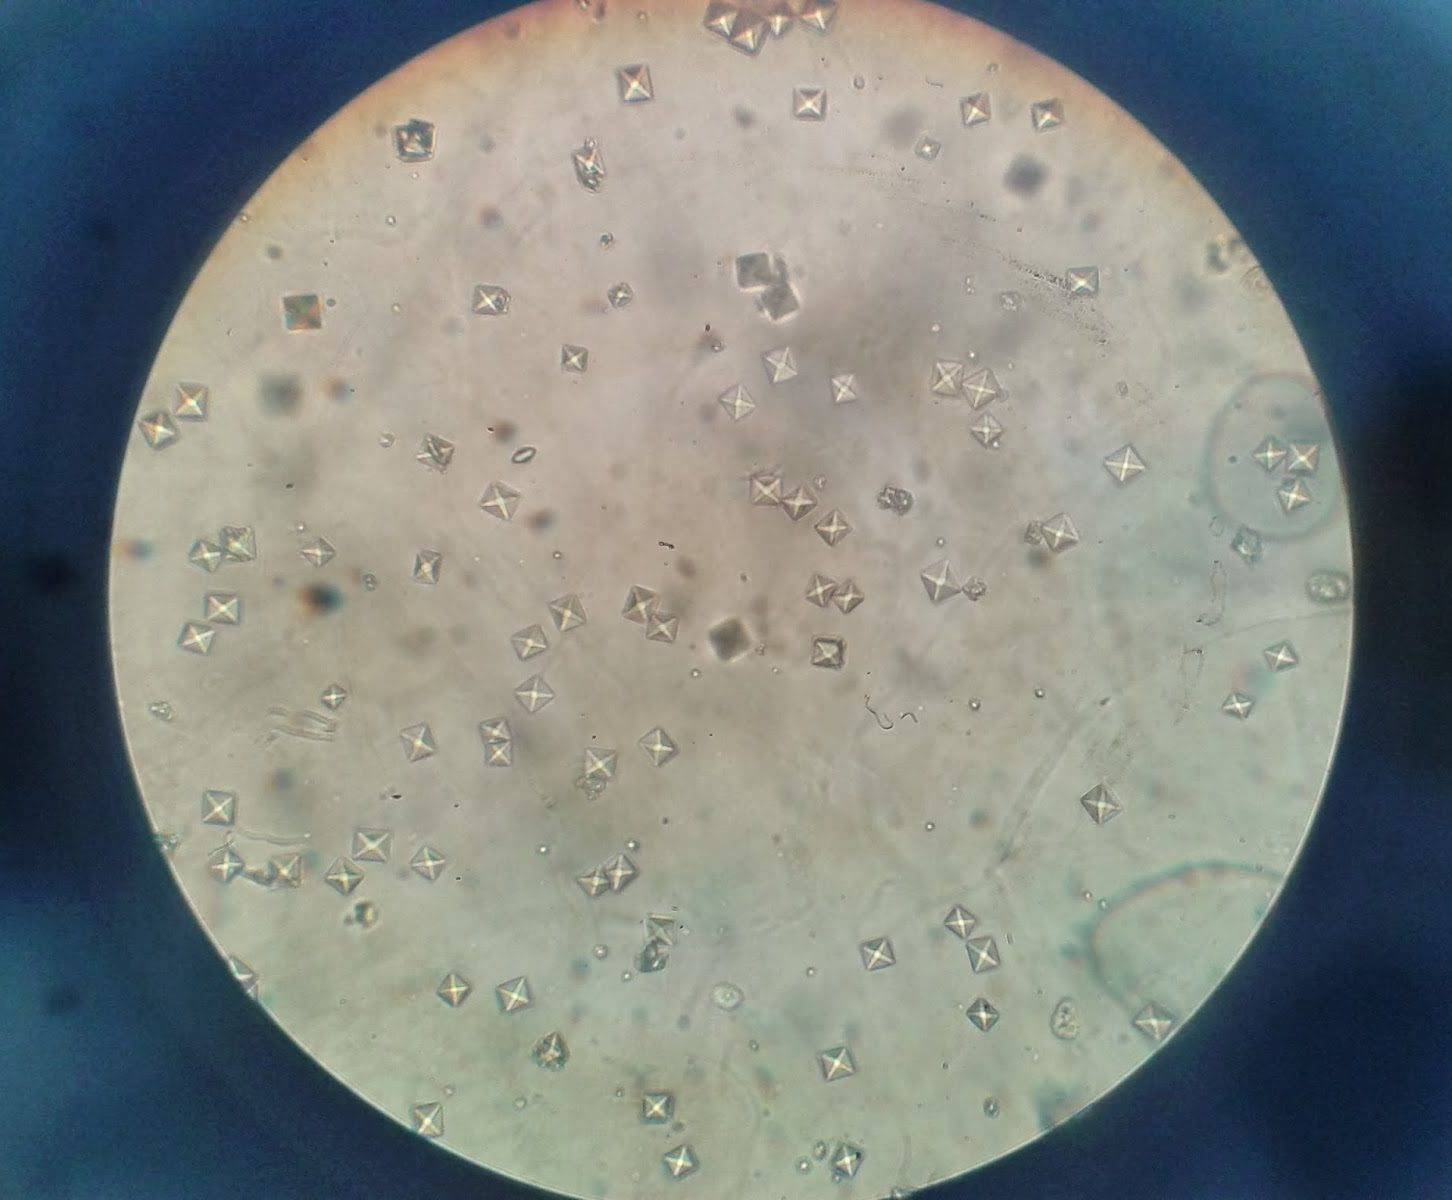

Кристаллы оксалата кальция под микроскопом

Крупицы оксалата натрия белые, довольно жесткие на ощупь. Они повреждают стенки мочевыводящих путей сильнее других, из-за чего грудничку может быть больно. Анализ мочи показывает наличие эритроцитов – кровяных клеток. Кроме того, эти кристаллы вредят почкам младенца.